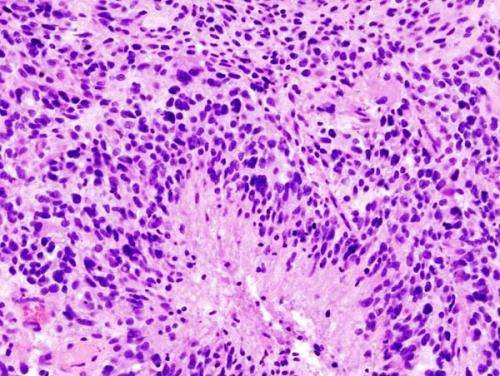

胶质母细胞瘤(组织学切片)